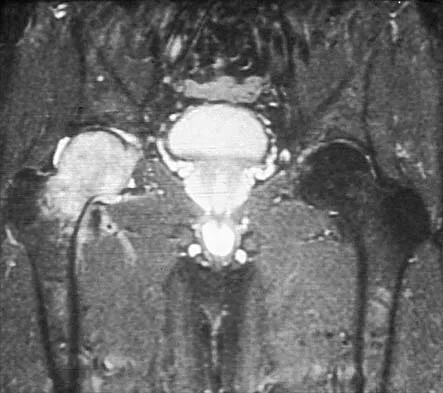

Figure 26 shows the MRI scan of a 60-year-old man who has had groin pain for the past 2 months. The patient reports pain with ambulation, and examination reveals an antalgic gait. He denies any history of steroid or alcohol abuse. Plain radiographs are normal. Management should include

Explanation